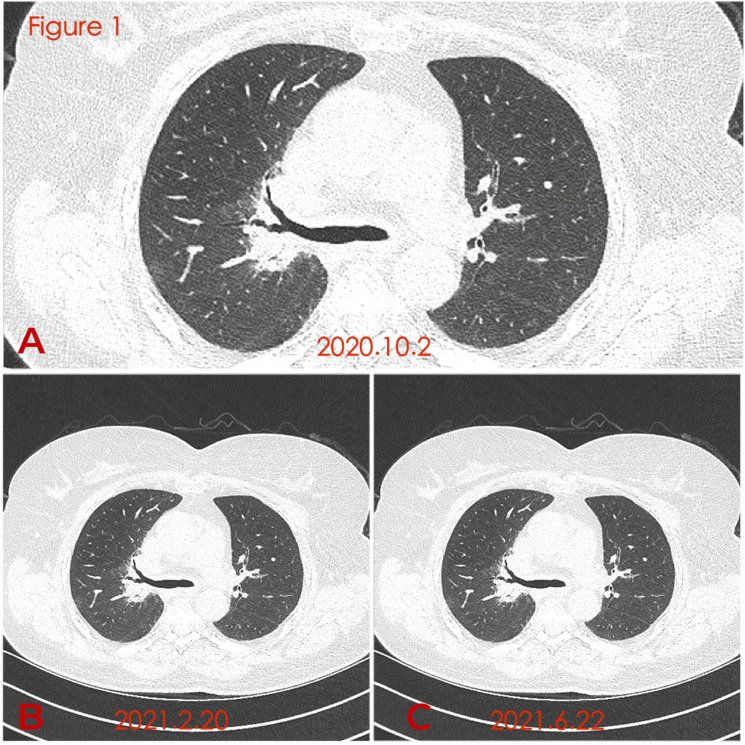

本研究报告了一例小细胞肺癌并发复发性多软骨炎的临床资料。我们报告一例57岁女性,表现为咳嗽、咳痰和发烧。在医院进行的计算机断层扫描显示双肺支气管壁弥漫性增厚。支气管镜检查显示气管黏膜增厚、变窄、塌陷,支气管镜可通过。两侧支气管黏膜增厚水肿,表面粗糙,各支气管狭窄,椎脊增宽。针活检:结合免疫组化结果考虑小细胞癌。经抗感染治疗后症状未见改善。住院期间左耳廓红肿,耳廓塌陷,左眼结膜下出血,无明显原因。经多学科会诊,考虑肺小细胞肺癌cT0N2Mx瘤胃淋巴结转移及RP。治疗:强的松,口服治疗RP。小细胞肺癌采用化疗与放疗联合治疗。化疗方案为卡铂联合依托泊苷。患者接受放化疗后已随访1年;目前病人的病情稳定。结合我们患者的病例,对于出现耳廓软骨炎、眼部炎性疾病、鼻软骨炎等症状的RP,我们要特别注意该病例是否由肺癌合并复发性多软骨炎引起。由于本病罕见,临床医师应提高对本病的认识,争取早期诊断和治疗。

The present study reports the clinical data of a patient with small cell lung cancer who developed relapsing polychondritis. We report a case of a 57-year-old female presented with cough, expectoration, and fever. A Computed Tomography (CT) scan performed at the hospital revealed diffuse thickening of bronchial walls in both lungs. Bronchoscopy revealed that the tracheal mucosa was thickened, narrowed, and collapsed, and the bronchoscope could pass through. The bronchial mucosa on both sides was thickened and edematous, the surface was rough, each bronchus was narrow, and the intervertebral ridges were widened. Needle biopsy: considering small cell carcinoma in combination with immunohistochemical results. Her symptom was not improved after anti-infective therapy. The left auricle was red and swollen, the auricle collapsed, and the left eye had subconjunctival hemorrhage during her hospitalization without obvious cause. After multidisciplinary consultation, pulmonary small cell lung cancer cT0N2Mx rumen lymph node metastasis and RP were considered. Treatment: Prednisone, orally for RP. Chemotherapy combined with radiotherapy was given for small cell lung cancer. The chemotherapy regimen was carboplatin combined with etoposide. The patient has already been followed for 1 year after receiving chemoradiotherapy; the condition of the patient is stable at present. Based on the case of our patient, for cases of RP with symptoms such as auricle chondritis, ocular inflammatory disease, and nasal chondritis, we should pay great attention to whether the case is caused by lung cancer with relapsing polychondritis. Because of the rarity of the disease, the clinician should improve the recognition of the disease in order to strive for early diagnosis and therapy.